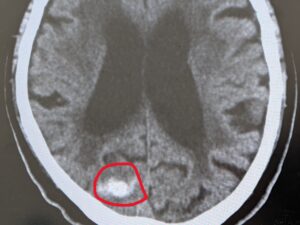

普段、近くの内科に高血圧の薬をもらいに通院している80代の男性の方です。

朝から頭が痛くて、近くの総合病院に受診しましたが

午後は外来やっていないと断れ、当院に受診されました。

頭部CTで脳出血を認め、総合病院に搬送しました。

血圧も170以上ありました。